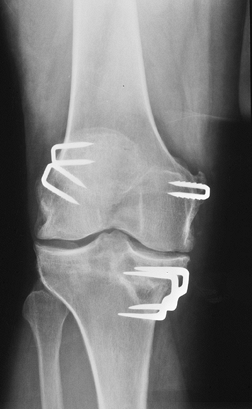

Ligament and Tendon Reconstruction

-

Complications include

Improper tunnel position

Hardware failure

Bone plug fracture

Patellar fracture (stress riser from donor site)

Graft (tendon) failure

Graft impingement

Anterior arthrofibrosis (cyclops lesion)

Postoperative infection

Routine radiographs should include AP,

MR images are obtained using routine knee

extended to evaluate for impingement.

![]() |

FIGURE 5-41 ACL repair with patellar tendon graft. (A) Patellar view showing bone donor site (arrow). (B) Notch view showing interference screws fixing the bone plugs. Graft tunnel positions (broken lines). (C) Lateral view demonstrating the tibial tunnel (broken lines) and tuberosity donor sight (arrow). (D) Cross-table lateral with extension showing the tibial tunnel (arrows) in proper position posterior to intercondylar roof (white line).

P.264

FIGURE 5-42 AP radiograph after ACL and MCL repairs. Staples fix the ends of the tendon grafts.